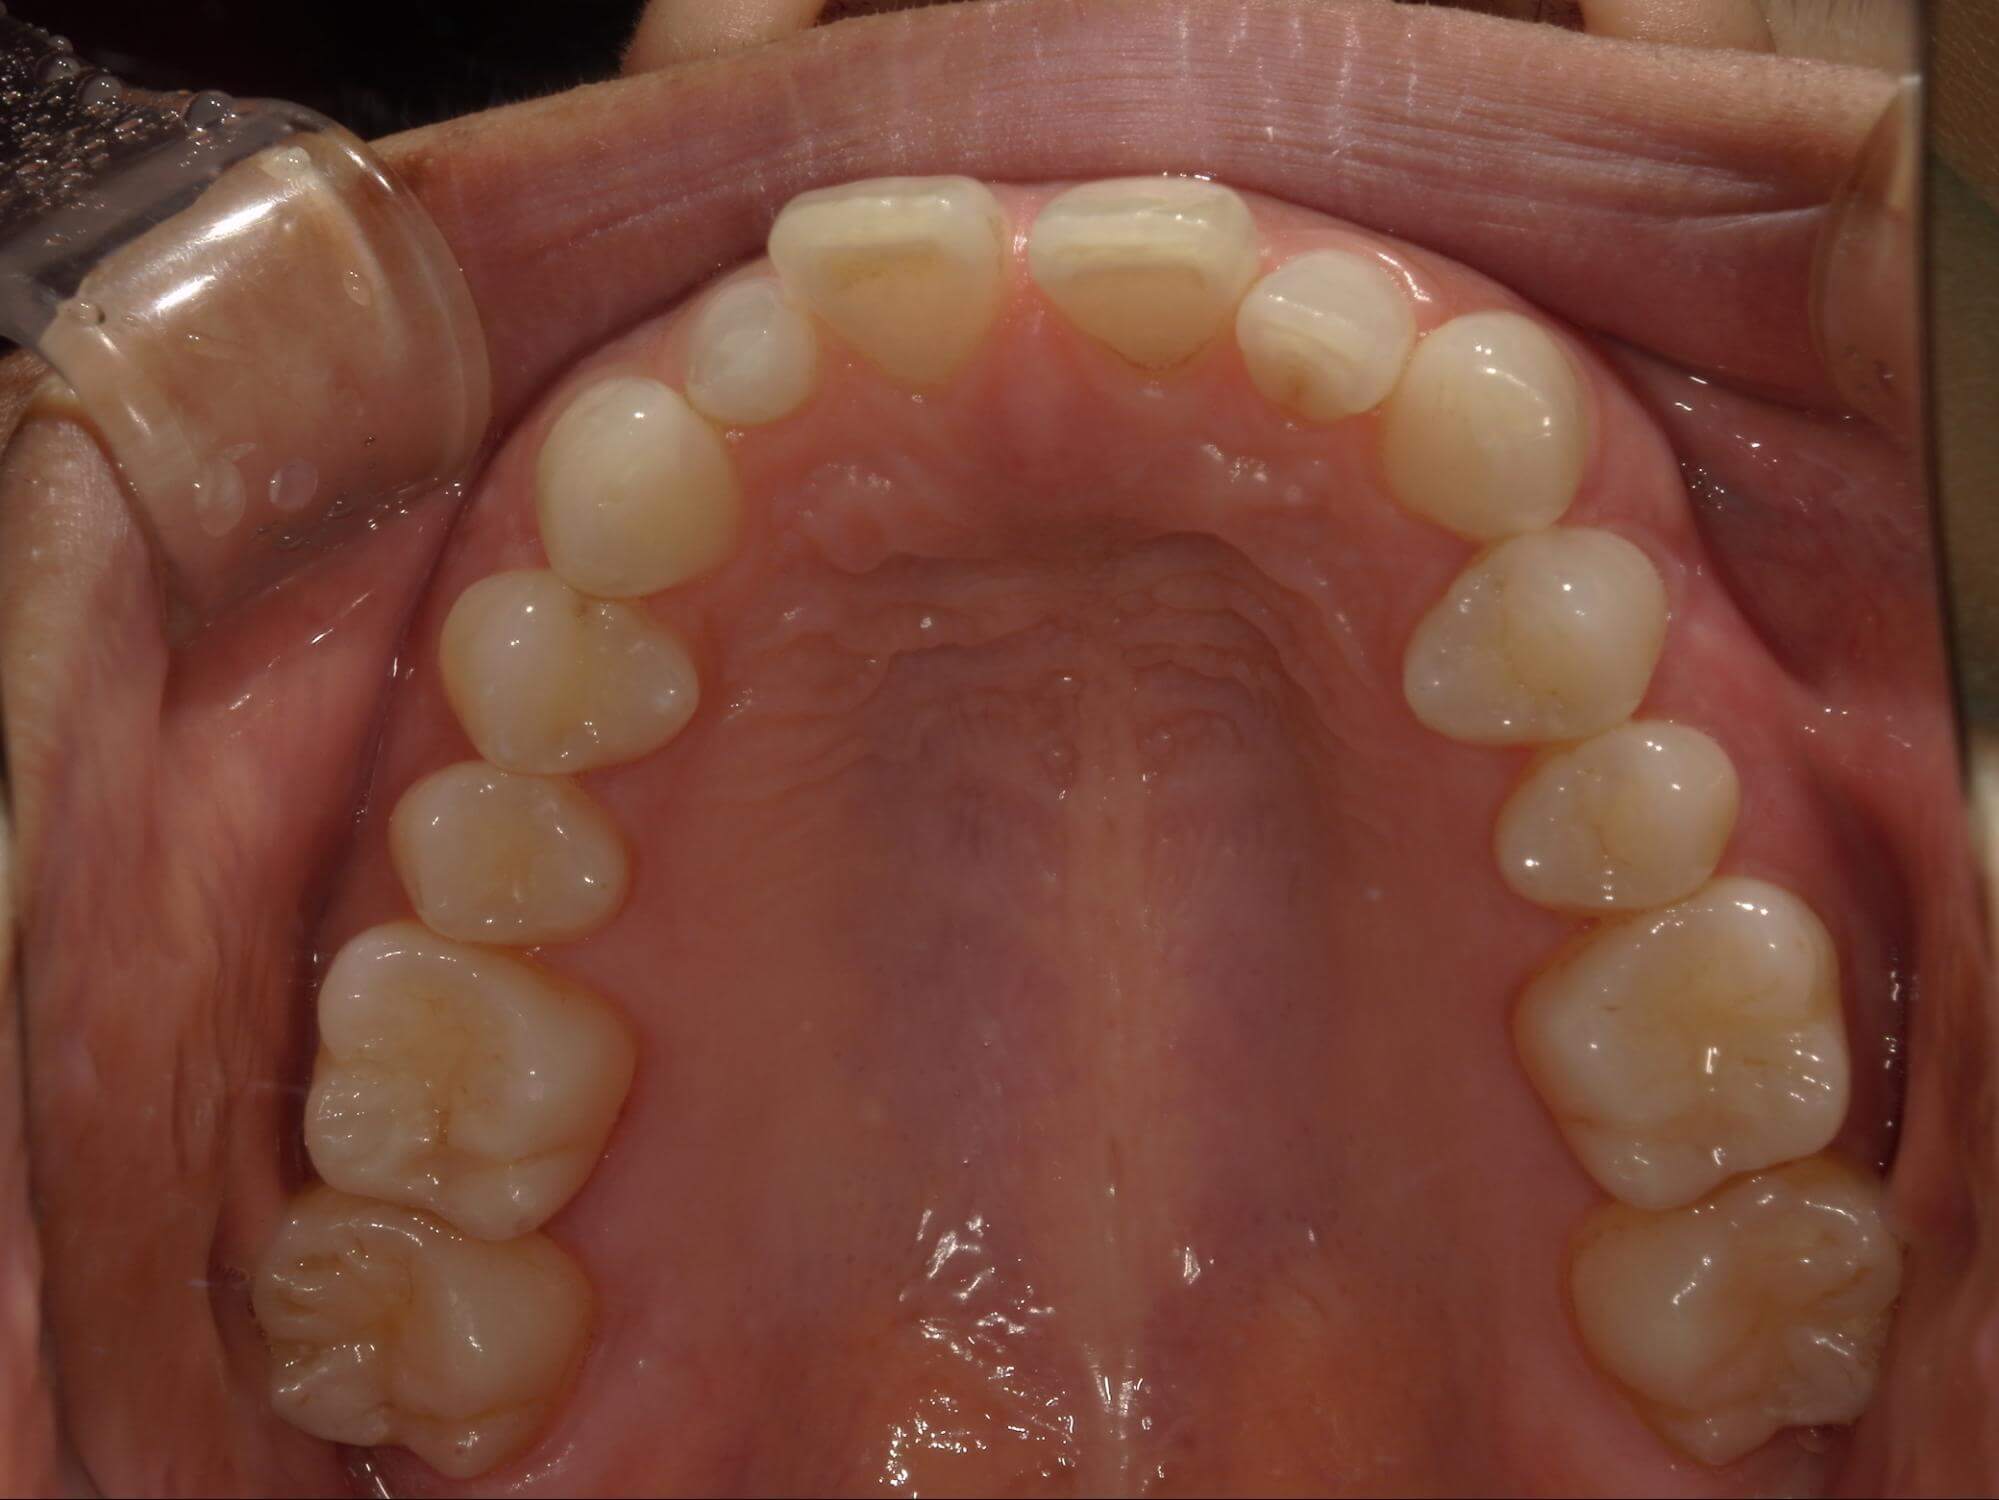

| 年齢・性別 | 21歳 |

|---|---|

| 主訴 | 叢生が気になる・前歯に埋伏歯がある |

| 治療期間・回数 | 6ヶ月 |

| 費用 | 935,000円 |

| 上顎の左側3番が埋伏していたため、上顎左右の3番および親知らずを抜歯し、矯正治療を行いました。 治療開始からおよそ6ヶ月で歯列が整い、審美的にも機能的にも良好な結果が得られた症例です。 |